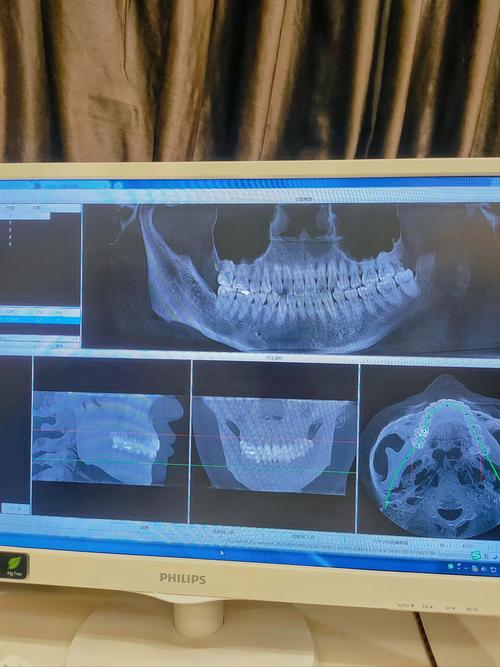

而CT(尤其是口腔专用的锥形束CT)通过三维重建技术,能生成牙齿、颌骨的立体模型,弥补二维影像的不足,具体而言,CT在矫正中的核心价值体现在以下方面:

- 图像处理:扫描完成后,电脑通过软件生成三维模型,医生可在工作站上任意切割、旋转图像,观察细节。